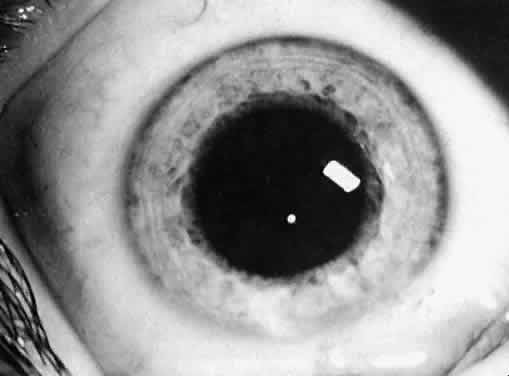

Not all cataracts require surgical treatment. Eyes with punctate or small anterior polar cataracts and others with partial opacification of the lens, such as posterior lenticonus, which only slightly interferes with the refraction of light, are best followed and not surgically treated (Fig. 1). In some cases, it is difficult to determine whether the presence of a partial cataract is responsible for a decrease in visual acuity or whether the refractive error or optical distortion produced by the cataract has produced a mild, reversible form of deprivation amblyopia. In these situations, correction of the refractive error and a trial of occlusion therapy should be attempted. If the visual acuity improves, it may be deduced that amblyopia was responsible for the loss of visual acuity and that the optical distortion produced by the partial cataract is not yet surgically significant.

Fig. 1. Cataracts that do not require surgical treatment. A. Anterior polar cataract. Visual acuity is 20/25. B. Partial punctate or cerulean cataract. Visual acuity is 20/30.

Type and Location

Usually, anterior polar cataracts are visually insignificant and allow normal visual development (see Fig. 1). However, some affect vision, and all require careful monitoring.7 Centrally located cataracts that are on or near the posterior lens capsule have a greater effect on the refraction of light and visual acuity (Fig. 2). Nuclear cataracts associated with metabolic disorders or prenatal infections produce double refracting systems that cause optical distortion and significantly decrease visual acuity (Fig. 3).